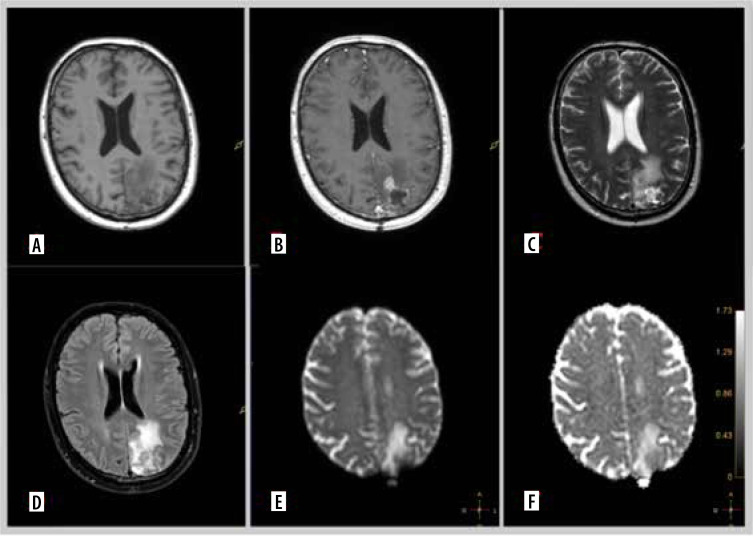

Material and methods: A total of 91 glioma patients treated between August 2023 and March 2024 were included in the analysis. All patients underwent preoperative magnetic resonance imaging (MRI), including DWI, and had available histopathological and genetic test results. Clinical data, tumour characteristics, and genetic markers such as IDH1 mutation, MGMT promoter methylation, EGFR amplification, TERT pathogenic variant, and CDKN2A deletion were collected. Statistical analysis was performed to identify correlations between ADC values, MRI perfusion parameters, and genetic characteristics.

Results: Significant associations were found between lower ADC values and aggressive tumour features, including IDH1-wildtype, MGMT unmethylated status, TERT pathogenic variant, and EGFR amplification. Additionally, distinct ADC patterns were observed in gliomas with CDKN2A, TP53, and PTEN gene deletions. These findings were further supported by contrast enhancement and other MRI parameters, indicating their role in tumour characterisation.